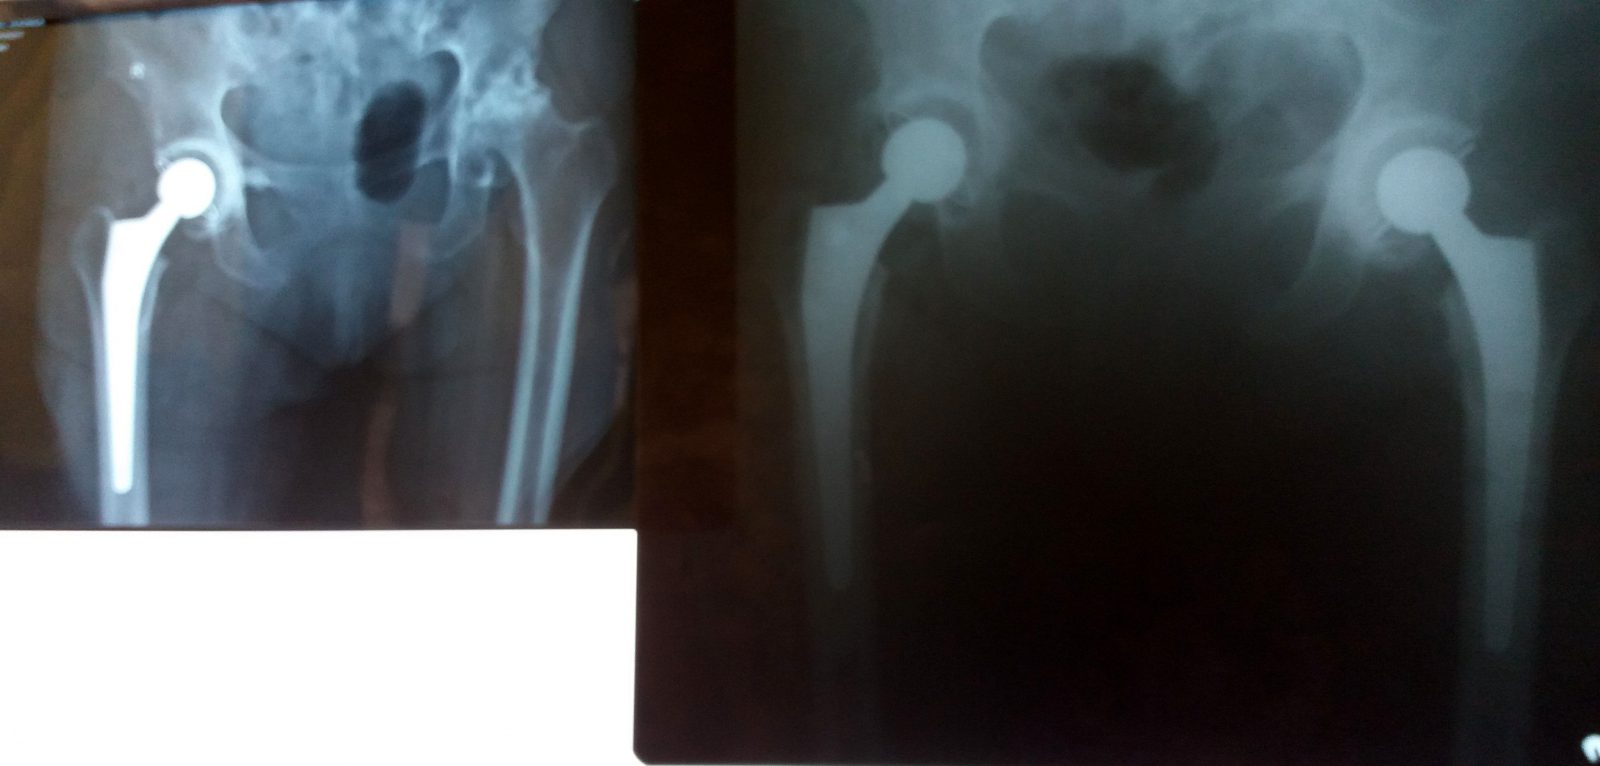

Medicii secției Ortopedie-Traumatologie din cadrul Spitalului Clinic Județean de Urgență “Sf. Apostol Andrei” Constanța au efectuat, în premieră, mai multe intervenții minim invazive pentru proteza de șold.

Abordul minim invaziv practicat în artroplastia totală de şold este o intervenție mai eficientă față de abordul clasic, sângerarea minimă și păstrarea intactă a mușchilor, care nu sunt secționați, fiind câteva dintre avantajele care duc la o recuperare rapidă și, implicit, o perioadă redusă de spitalizare, spun medicii spitalului.

Până acum, la SCJU “Sf. Apostol Andrei” Constanța au fost efectuate patru intervenții de acest gen, ultimul pacient fiind o femeie în vârstă de 75 de ani, căreia i-au fost montate două proteze de șold în cadrul aceleiași internări, perioada de spitalizare fiind de maximum zece zile. Intervențiile minim invazive cu abord anterior pentru proteza de șold sunt efectuate la SCJU, în momentul de față, doar de către dr. Băjenescu Titi Marian și dr. Alexandru Șerban, medicul șef al secției Ortopedie-Traumatologie.